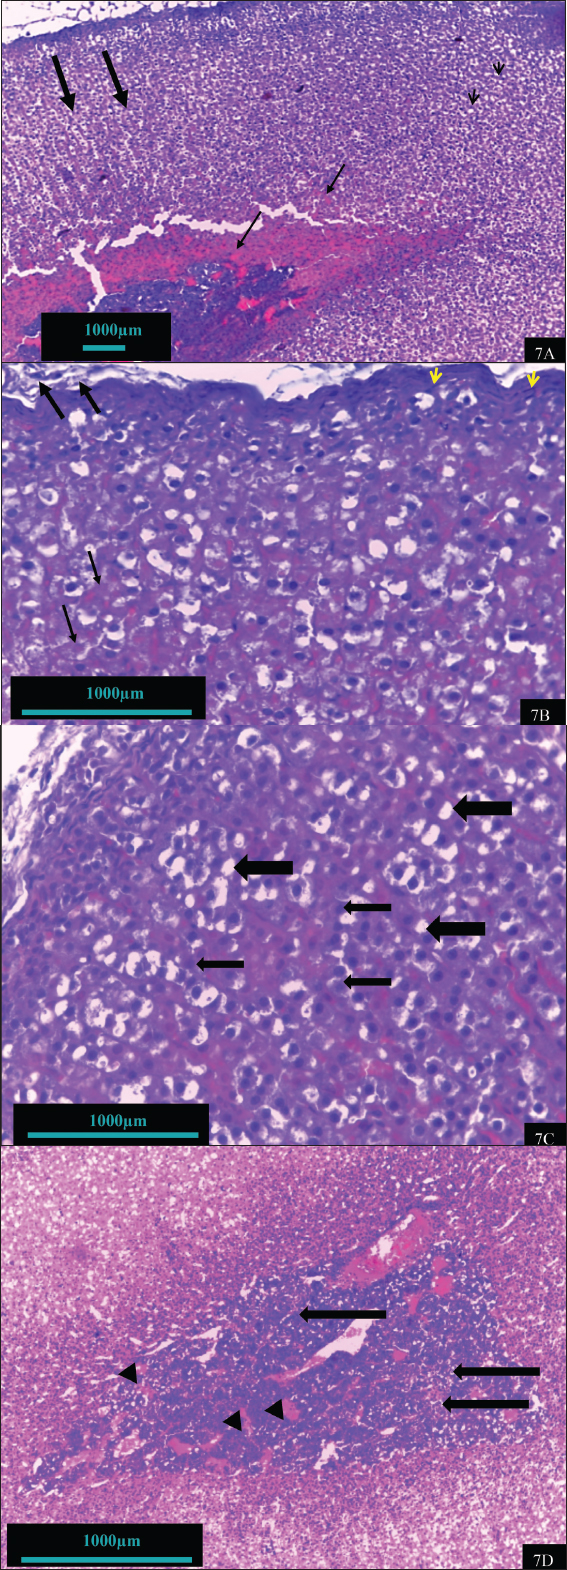

In contrast, the adrenal gland of hypothyroid rats treated with vitamin B12 (hypothyroid + B12) exhibited a notable reparative feature (Fig. 7). Improvements include enhanced capsule integrity, normalization of adrenal cells with clear visible, light-colored nuclei, and restoration of the cellular boundary and cytoplasm. The cell size and number of the cortex and medulla are nearly normal. The features observed in this group are depicted in the control group. The adrenal tissue of rats treated with vitamin B12 exhibited remarkable tissue similarity with the control group (Fig. 8).

Fig. 8. Histomorphohogy of adrenal gland tissues in the vitamin B12 group showing normal capsule (thick arrow), surrounding adipose tissue (arrowhead), normal layers of adrenal cortex (thin arrow), and adrenal medulla (curved arrow) (8A) (100X). The zona glomerulosa cells showed active nuclei (thick arrow), and the cells of the fasciculate layer are arranged in the form of fascicule (thin arrow) (8B) (400X).